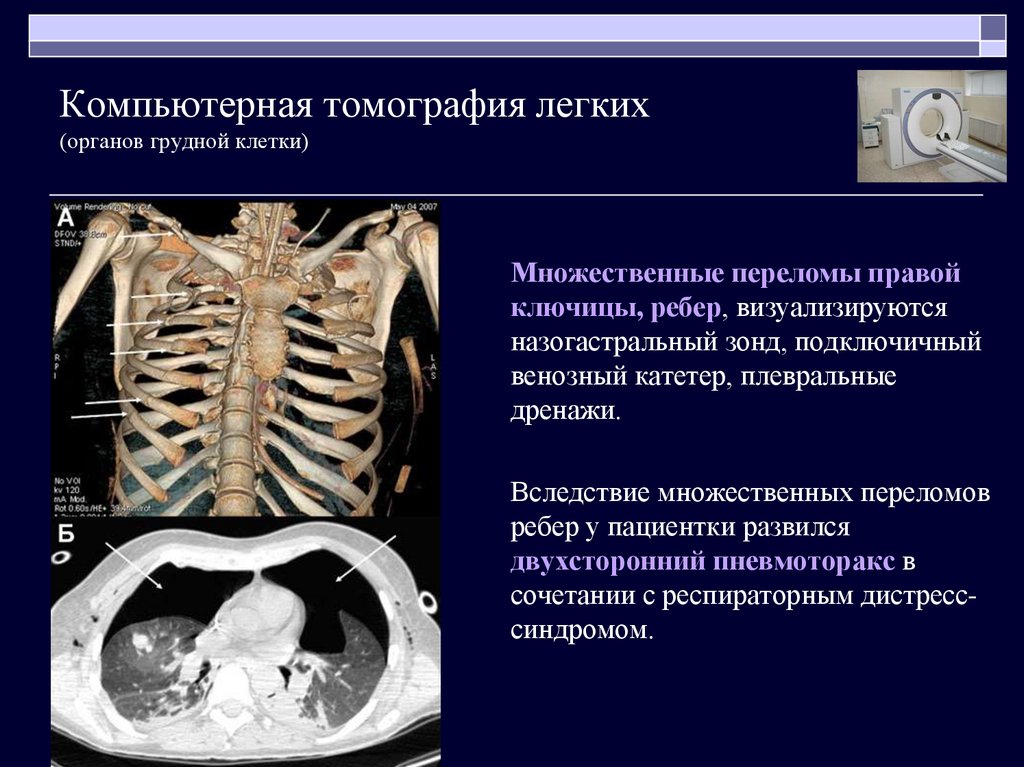

Травма органов грудной клетки на примере клинических случаев

Компьютерная томография (КТ) грудной полости

Мультиспиральная КТ в диагностике тупой торакальной и абдоминальной травмы